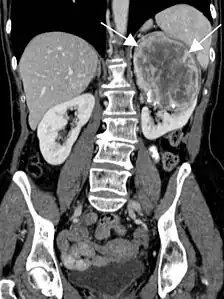

En tomodensitométrie[20],[31], quelle que soit la localisation, une tumeur fibreuse solitaire apparaît comme une masse tissulaire ovoïde ou lobulée, bien délimitée, refoulant les structures voisines sans les envahir. Elle se rehausse fortement après injection de produit de contraste. Les tumeurs de petite taille sont homogènes, mais les plus volumineuses présentent des plages hétérogènes de nécrose et d'hémorragie intra-tumorale. Il n'y a pas habituellement de calcifications et, lorsqu'elles sont présentes, elles sont de petite taille[31]. Les tumeurs malignes peuvent se présenter accompagnées de nodules pulmonaires métastatiques, et tendent à être plus volumineuses et plus hétérogènes[42].